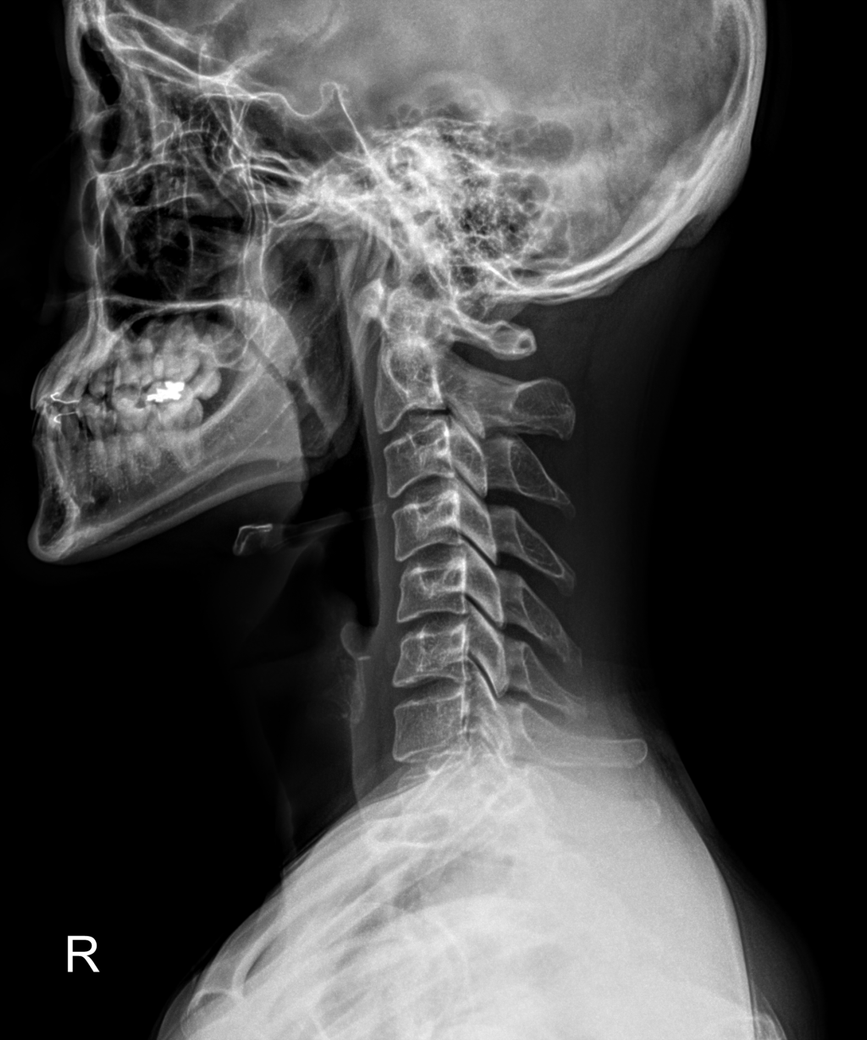

목 xray찍어봤는데 거북목 많이 심한건가요? 부탁드립니다..

무거운 옷을 입고 자주 나갔더니 어깨 통증이 있어서 근처 정형외과에서 x-ray를 찍어봤는데요

아래 사진처럼 나왔습니다.

의사선생님께서는 거북목이 엄청 심하다고, 나이가 있어서 완벽한 교정에 회의적이라 하셨구요

물리치료사분께서는 근래 본 거북목 환자 중에 가장 심하다면서 주 3회 도수 치료 받자고 하셨어요...

거북목인건 알았는데 그렇게 심한건가요...?

목 뼈는 정상적으로 C자 모양을 보여야하는데, 질문자 님은 목뼈가 일자 또는 약한 역 C자 형태로 심한 거북목에 해당합니다.